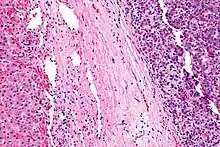

| Micrograph of a hepatoblastoma. H&E stain. | |

Hepatoblastoma is a malignant liver cancer occurring in infants and children and composed of tissue resembling fetal liver cells, mature liver cells, or bile duct cells. They usually present with an abdominal mass. The disease is most commonly diagnosed during a child's first three years of life.[1] Alpha-fetoprotein (AFP) levels are commonly elevated, but when AFP is not elevated at diagnosis the prognosis is poor.[2]

Hepatoblastomas originate from immature liver precursor cells, are typically unifocal, affect the right lobe of the liver more often than the left lobe, and can metastasize. They are categorized into two types: "Epithelial Type" and "Mixed Epithelial / Mesenchymal Type."